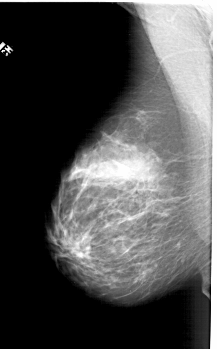

A_1394_1.LEFT_MLO

LEFT_MLO LINES 5926 PIXELS_PER_LINE 3676 BITS_PER_PIXEL 12 RESOLUTION 43.5 NON_OVERLAY